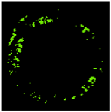

Since clustering algorithms will not return the same cluster index value every time, the colour of each cluster should be determined. With respect to the colour of each cluster, its matching plaque components can be determined as NC: red, DC: white, FI: dark green, and FF: light green [45].

Class label of each colour feature should be determined to perform the pixel wise classification [73]. The non-zero pixels in DC, NC, FF, and FI images were saved into CF matrix. Their corresponding labels were calculated and saved into the vector L [45].

Four colour images representing the plaque components are provided using the assigned label during the pixel classification process. The area of each plaque component can be calculated based on the number of non-zero pixels in each image. The area of NC, DC, FF, and FI images can be represented as tissue area features of fNC, fDC, fNC, fFF, and fFI, respectively. These values are considered to be the primary features for TCFA detection.